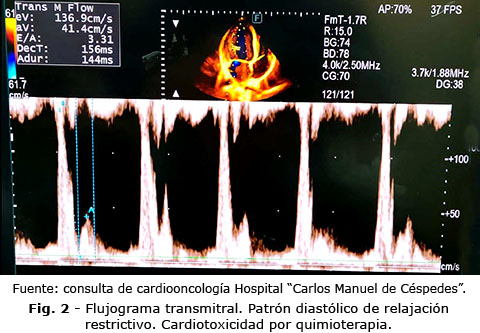

Aún así, su valor fisiopatológico potencial no debe subestimarse. En la era de la cardiotoxicidad con FEVI preservada, la identificación de disfunción diastólica precoz es crucial para intervenir antes de la aparición de síntomas.(3,4) La integración del FVP dentro de un modelo multimodal que combine GLS, biomarcadores (troponina, NT-proBNP) y medidas de presión de llenado, como el flujograma transmitral y el TDI, podría mejorar la estratificación del riesgo y la predicción de insuficiencia cardiaca con fracción de eyección preservada (ICFEp) en supervivientes de cáncer. Estudios como Fawzy AA y otros(13) demuestran que la evaluación con técnicas ecocardiográficas avanzadas (strain, 3D, enfoque del ventrículo derecho) sigue en expansión, aunque no analizan explícitamente flujo de venas pulmonares, refuerzan la necesidad de multimodalidad(13) (Fig. 2).

La estimación del FVP mediante Doppler pulsado ha sido históricamente empleada para valorar la función diastólica y la interacción auriculoventricular. El patrón normal muestra dos ondas principales: una sistólica (S) y una diastólica (D), seguidas de una reversa auricular (Ar). Las modificaciones de la relación S/D y la prolongación de la onda Ar se correlacionan con el aumento de la presión de llenado y la rigidez del ventrículo izquierdo (Fig. 1). Por tanto, teóricamente, el FVP podría reflejar cambios tempranos en la función de llenado antes de la alteración de la FEVI o del GLS en pacientes expuestos a quimioterapia cardiotóxica.(9,10)